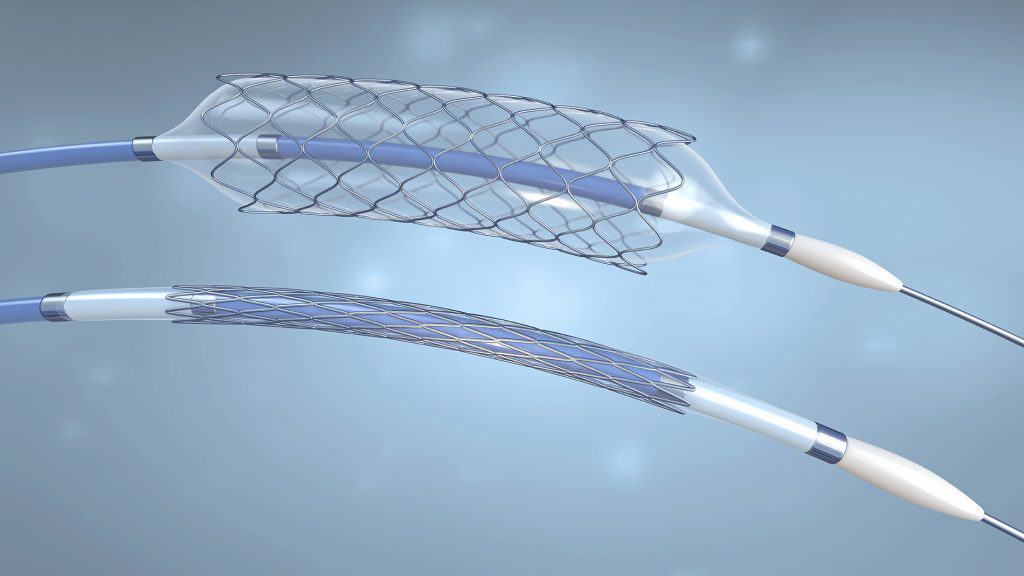

Balloons

HOOP Company specializes in the development and manufacture of advanced medical balloon components for the global medical device industry. The company offers a diverse range of balloons, encompassing non-compliant (non-stretchy) and ultra-compliant (very stretchy) options in various shapes and sizes.

HOOP Company maintains a robust inventory of popular balloon materials, including Nylon, PET, Pebax, Polyurethanes, and TPEs, allowing for swift fulfillment of custom requirements. Their state-of-the-art robotic blow molding process can be optimized to achieve specific design targets, such as thin walls, high burst pressures, and compact crossing profiles, delivering truly custom balloon components within a short lead time.

The company can efficiently blow mold balloons using a wide range of medical-grade thermoplastic materials. HOOP Company is equipped to assist clients in selecting the appropriate polymer to enhance balloon performance and ensure seamless integration with medical devices and assembly processes.